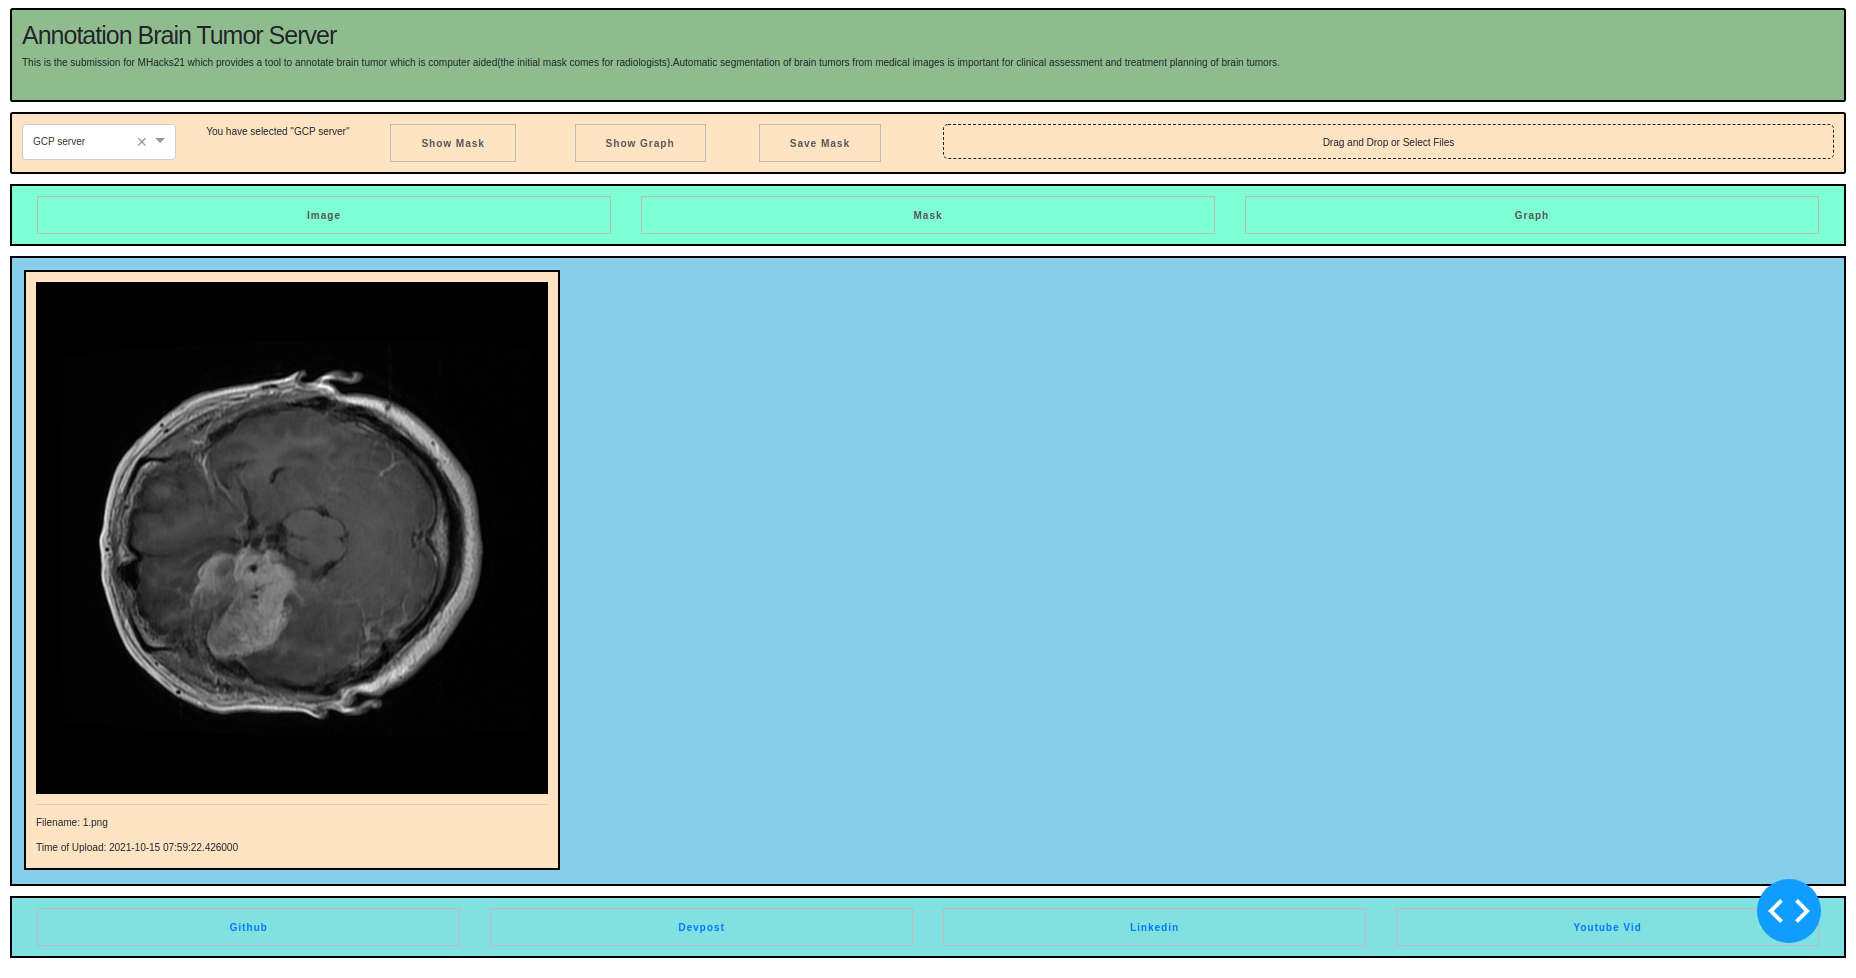

Load a image using drag & drop or select files

Then it's mask will be automatically found using the inference model, use show mask to see the mask of the brain tumor

Click on show graph now, it shall show a dash plotly for you to edit and work with the mask

Yeah, then it can zoomed, using closed freeform tool..it can be manipulated, and also can be saved

It provides a computer aided brain tumor segmentation annotation tool for radiologists to reduce the errors and help with their work.